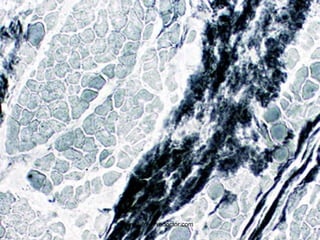

• #6 SILVER STAIN showing black axons surrounded by washed out fat (myelin)

• #7 MYELIN stain showing the REVERSE of the previous slide